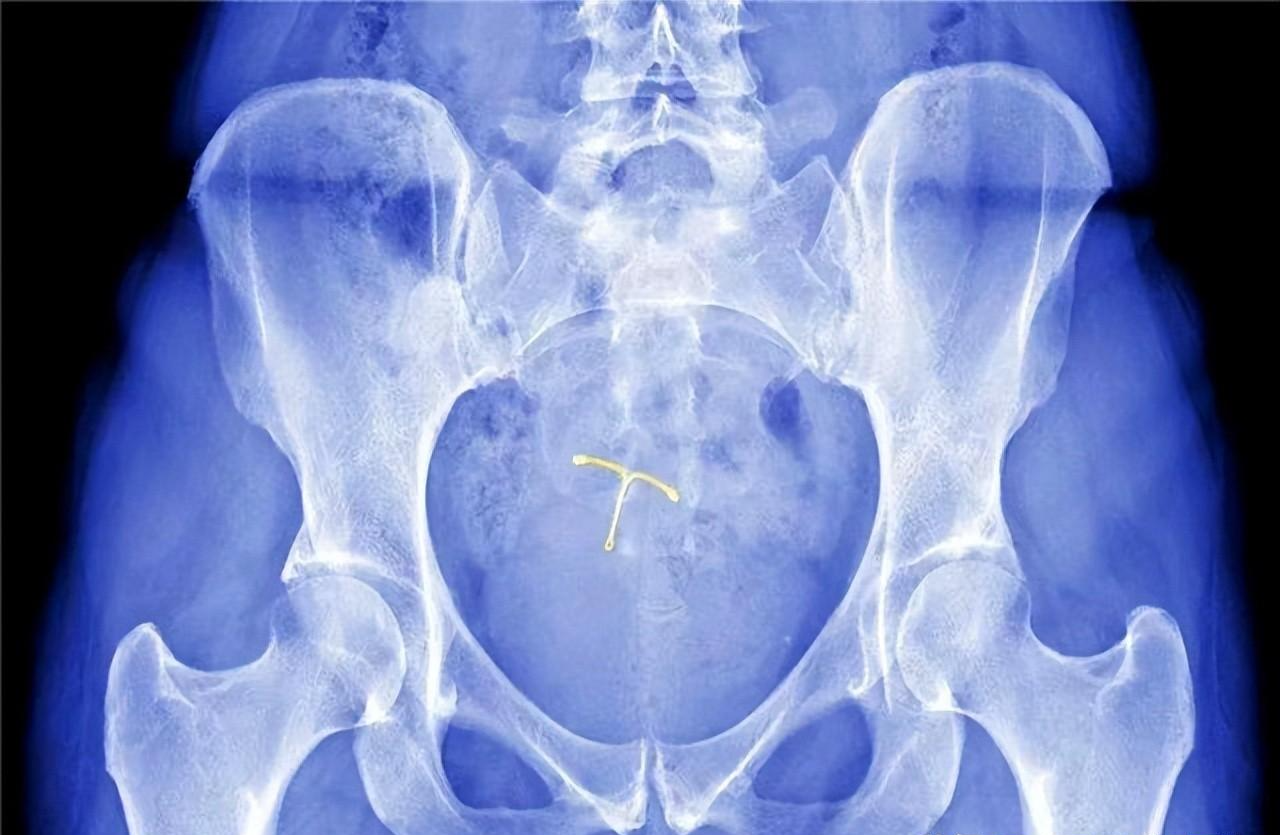

通过腹部影像检查发现李女士子宫内的节育环嵌顿至子宫基底 , 而且在周围形成大量脓性物质 , 询问李女士节育环使用年限是否到期 , 放置节育环后有无复查 , 通过林女士的回答得知节育环已到期 , 而且李女士并没有复查过 , 最终确诊为是由节育环嵌顿导致的子宫腔内感染 。

通过会诊确定李女士的治疗方案 , 通过手术摘除节育环的方式来避免子宫腔再次感染 , 术后及时服用消炎药物 , 由于李女士节育环嵌顿较深 , 手术摘除后可能存在出血现象 , 术后一周需保持严格卧床休息 , 出血严重时可适量使用止血药物 , 摘出手术非常成功 , 半个月后李女士逐渐恢复正常 。